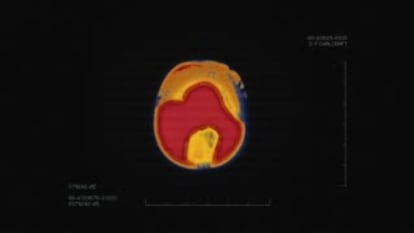

A continuación, ejemplos de la lucha de las organizaciones contra el alzhéimer de todo el mundo por visibilizar, más si cabe, el problema. Al principio, todo comienza con un escáner...